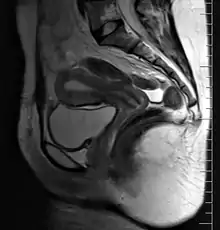

Female reproductive system

The female reproductive system is made up of the internal and external sex organs that function in the reproduction of new offspring. In humans, the female reproductive system is immature at birth and develops to maturity at puberty to be able to produce gametes, and to carry a fetus to full term. The internal sex organs are the vagina, uterus, fallopian tubes, and ovaries. The female reproductive tract includes the vagina, uterus, and fallopian tubes and is prone to infections.[1] The vagina allows for sexual intercourse and childbirth, and is connected to the uterus at the cervix. The uterus or womb accommodates the embryo which develops into the fetus. The uterus also produces secretions which help the transit of sperm to the fallopian tubes, where sperm fertilize ova (egg cells) produced by the ovaries. The external sex organs are also known as the genitals and these are the organs of the vulva including the labia, clitoris, and vaginal opening.[2]

9. Vagina: 10. Hymen; 11. Lumen; 12. Wall; 13. Fornix (lateral)

14. Uterus: Parts: 15. Cervix; 16. Body and 17. Fundus. 18. Orifices: External and Internal; 19. Cervical canal; 20. Uterine cavity; Layers: 21. Endometrium; 22. Myometrium and 23. Perimetrium

24. Fallopian tube: 25. Isthmus; 26. Ampulla; 27. Infundibulum; 28. Fimbria (with 29. Fimbria ovarica)

30. Ovary

31. Visceral pelvic peritoneum: 32. Broad ligament (with 33. Mesosalpinx; 34. Mesovarium and 35. Mesometrium)

Ligaments: 36. Round; 37. Ovarian; 38. Suspensory of ovary

Blood vessels: 39. Ovarian artery and vein; 40. Uterine artery and veins; 41. Vaginal artery and veins

Other: 42. Ureter; 43. Pelvic floor (Levator ani); 44. Femoral head; 45. Hip bone; 46. Internal iliac vessels (anterior branches); 47. External iliac vessels; 48. Abdominal cavity